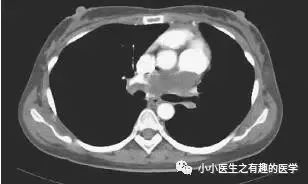

首先,来看看这个患者。美国康涅狄格州立大学报道,58岁男性,咳嗽,劳力性呼吸困难,进行性双侧下肢水肿2月。

A 58-year-old man presented with 2 months of cough, dyspnea on exertion, and progressive bilateral lower extremity edema.

这是什么?妥妥的肺栓塞啊,还能有啥?

怎么办?肿么办?别慌,米国人民的治疗和我们一样。抗凝治疗,2周后,患者呼吸困难加重返院。

He was treated expectantly with anticoagulants for pulmonary embolism but returned 2 weeks later with worsening dyspnea and echocardiographic evidence of right heart failure.